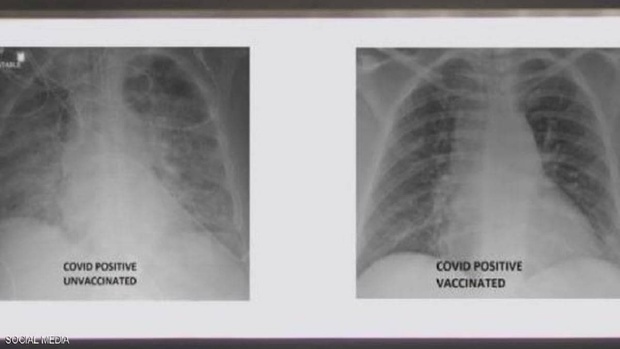

یک پزشک آمریکایی تصویری را از ریه های فرد واکسینه شده و فرد واکسینه نشده مبتلا به کرونا منتشر کرد.

جی پلاس، به نقل از اسکای نیوز، غسان کمال پزشک عرب در ایالات متحده، تصویری را منتشر کرد که تفاوت بین ریه‌های فردی که در برابر ویروس کرونا واکسینه شده بود، با ریه‌های شخص دیگری که واکسن دریافت نکرده بود به نمایش گذاشت و نشان می‌دهد هر دو نفر به ویروس کرونا مبتلا شده اند.

تصاویر اشعه ایکس نشان می‌دهد که ریه‌های فرد واکسینه نشده آلوده به ویروس کرونا تقریباً سفید بوده و به عنوان "تیرگی ریه" شناخته می‌شود، به این معنی که آن‌ها در این ویروس آغشته شده اند، در حالی که تصاویر ریه‌های فرد دیگر سفیدی کمتری دارد.

تصویر مورد اول همچنین به معنای کمبود هوا در ریه‌های فرد است، در حالی که در مورد دوم به این معنی است که هوا به راحتی جریان می‌یابد، علاوه بر این ریه‌های او عاری از ویروس است.